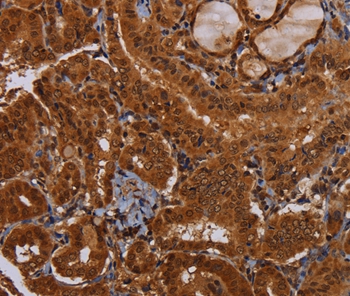

Immunohistochemical analysis of paraffin-embedded Human thyroid cancer tissue using #36600 at dilution 1/30.